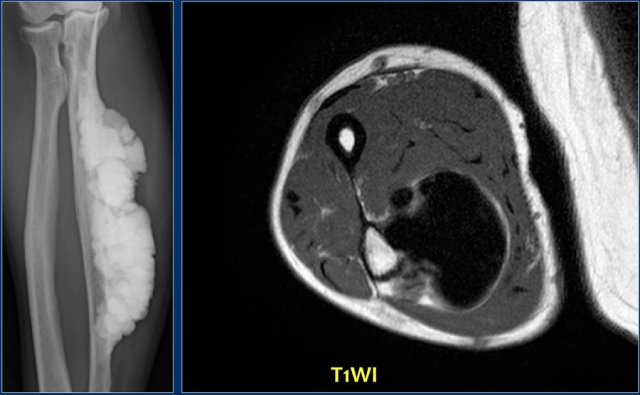

Here Melorrheostosis of the ulna with the appearance of candle wax.

A surface osteosarcoma could be considered in the differential diagnosis

Axial T1-weighted MR image shows homogeneous low signal intensity due to the compact bone apposition.